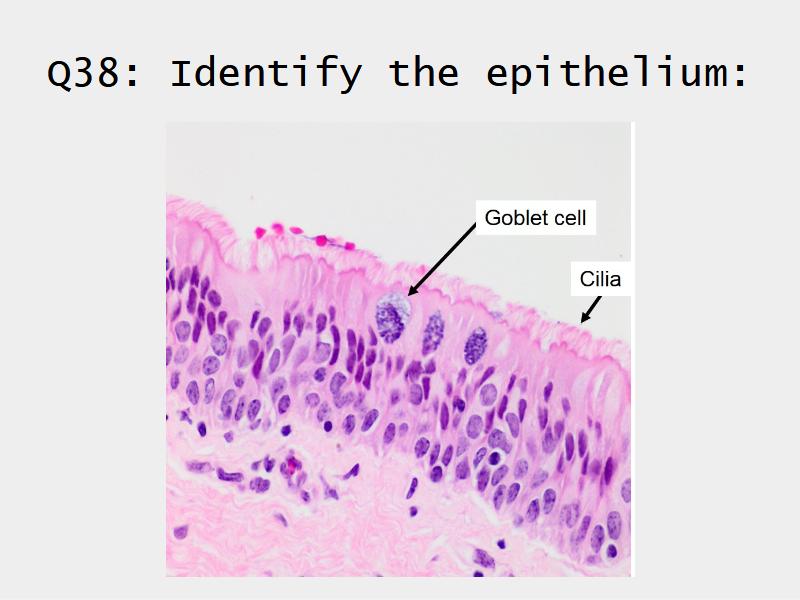

Respiratory epithelium

- Pseudostratified

- Ciliated

- Columnar

- Epithelium with

- 4 Cells

- Ciliated columnar cells

- Non-ciliated columnar cells

- Goblet cells

- Basal cells